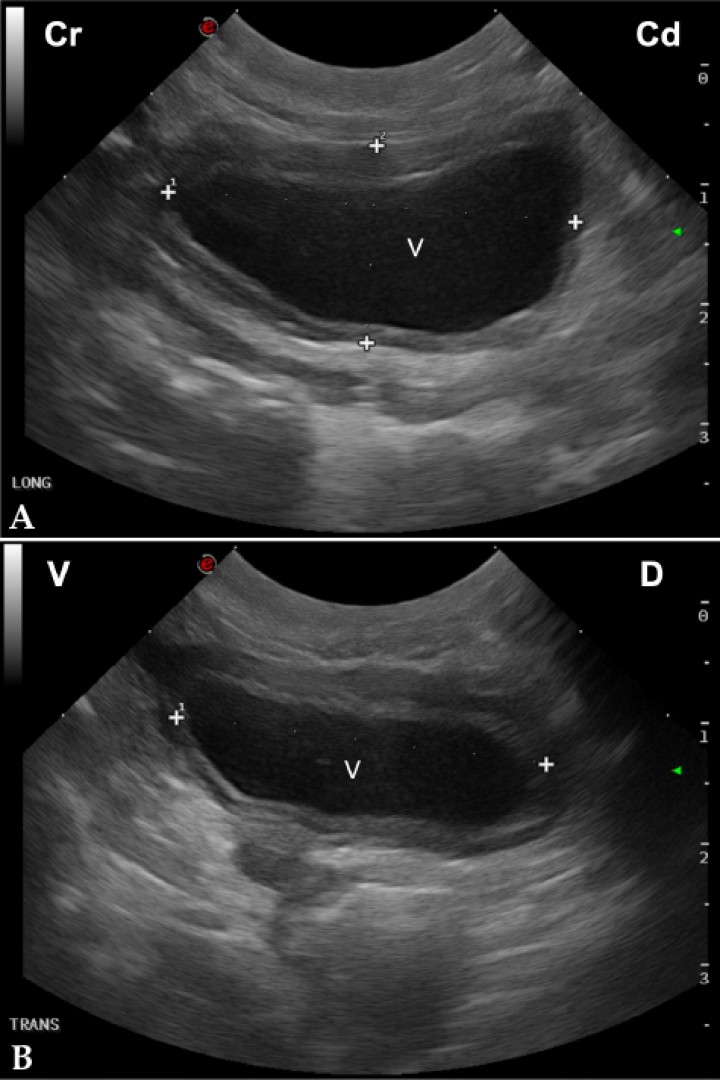

¿Cómo valorar el volumen de la vejiga en pacientes críticos?

El output de orina puede dar una información importante en los animales hospitalizados, ya que guiará la modificación del protocolo de fluidoterapia y aportará información sobre la función renal.[ Nicolaou S, Talsky A, Khashoggi K, Venu V: Ultrasound-guided interventional radiology in critical care. Crit Care Med 2007; 35: S186-S197. [PubMed] ] Dicha medición puede determinar si el paciente está produciendo volúmenes aceptables de orina o no.[ Lisciandro GR, Fosgate GT: Use of urinary bladder measurements from a point-of-care cysto-colic ultrasonographic view to estimate urinary bladder volume in dogs and cats. J Vet Emerg Crit Care 2017; 27(6): 713-717. [PubMed] ] En el estudio realizado en 2017 por Lisciandro et al. se desarrolló una fórmula para estimar el volumen de la vejiga urinaria basada en medidas que se adquirían durante la A-FAST en la unión cistocólica en perros y gatos machos.[ Lisciandro GR, Fosgate GT: Use of urinary bladder measurements from a point-of-care cysto-colic ultrasonographic view to estimate urinary bladder volume in dogs and cats. J Vet Emerg Crit Care 2017; 27(6): 713-717. [PubMed] ] Dicha fórmula consistía en obtener la longitud máxima y la altura de la vejiga urinaria, usando la orientación sagital de la sonda (corte sagital de la vejiga; Fig. 7A) y el ancho máximo rotando la sonda 90º (corte transversal; Fig. 7B):

Longitud (cm) x Ancho (cm) x Altura (cm) x 0,2 π9

<p>(<strong>A</strong>) Imagen longitudinal de la vejiga. La distancia entre los calipers marcados con un 1 mide la longitud de la vejiga (V), mientras que los marcados con un 2 muestran la altura de la misma. Cr: craneal; Cd: caudal. (<strong>B</strong>) Imagen transversal de la vejiga. La distancia entre ambos calipers mide el ancho de la vejiga (V). V: ventral; D: dorsal.</p>

Figura 7

(A) Imagen longitudinal de la vejiga. La distancia entre los calipers marcados con un 1 mide la longitud de la vejiga (V), mientras que los marcados con un 2 muestran la altura de la misma. Cr: craneal; Cd: caudal. (B) Imagen transversal de la vejiga. La distancia entre ambos calipers mide el ancho de la vejiga (V). V: ventral; D: dorsal.

Es importante tener en cuenta que esta fórmula tiende a subestimar los volúmenes de orina en vejigas con menos de un 10 % de llenado vesical. También presenta algunas limitaciones como, por ejemplo, su uso en vejigas con presencia de masas u otros procesos que alteren la forma de la misma, por lo que la estimación del volumen será menos preciso.[ Lisciandro GR, Fosgate GT: Use of urinary bladder measurements from a point-of-care cysto-colic ultrasonographic view to estimate urinary bladder volume in dogs and cats. J Vet Emerg Crit Care 2017; 27(6): 713-717. [PubMed] ] Esta fórmula es más exacta cuando se usa con tamaños normales de vejigas, pudiendo no ser muy precisa con vejigas pequeñas o muy distendidas.[ Lisciandro GR, Fosgate GT: Use of urinary bladder measurements from a point-of-care cysto-colic ultrasonographic view to estimate urinary bladder volume in dogs and cats. J Vet Emerg Crit Care 2017; 27(6): 713-717. [PubMed] ]